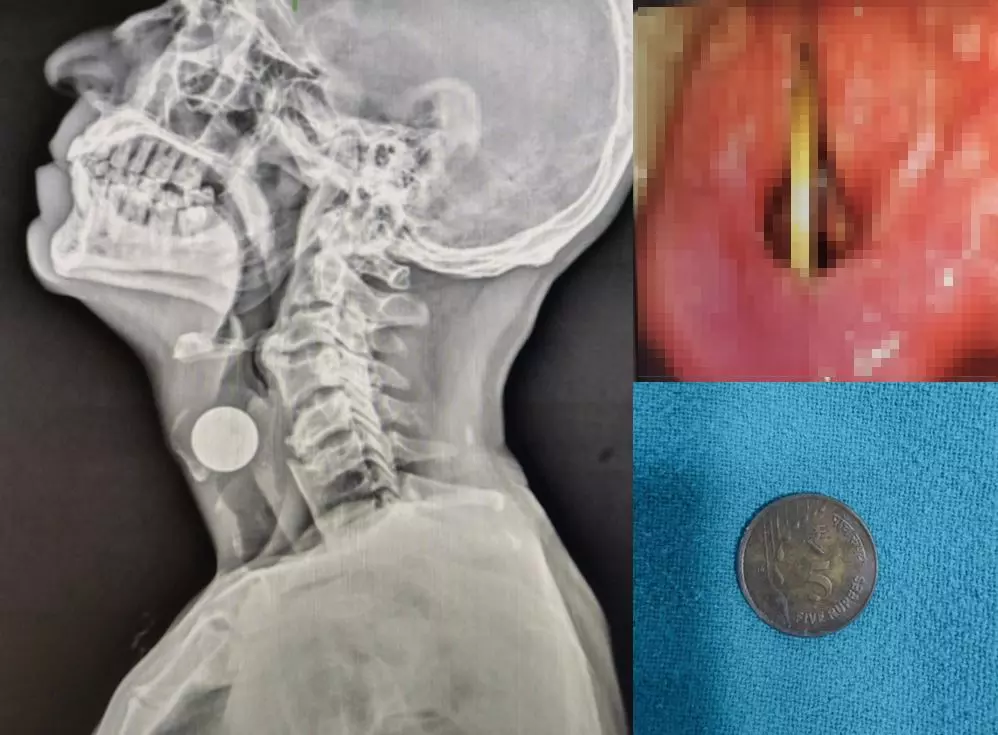

정확한 진단을 위해 경직 후두경 검사와 엑스레이 검사를 시행한 결과, 원형 이물질이 두 성대 사이에 수직으로 박혀 있는 것이 확인됐다. 이는 환자가 삼킨 동전 중 하나였다. 추가로 흉부·복부 엑스레이 촬영을 시행한 결과, 위장관에서도 여러 개의 동전이 발견됐으며, 해당 동전들은 이후 합병증 없이 대변으로 자연 배출된 것으로 전해졌다.

의료진은 갑작스러운 기도 폐쇄 위험을 고려해 긴급 후두경 검사를 시행해 동전을 조심스럽게 제거했다. 제거 직후 점막은 손상은 발견되지 않았고 성대 운동도 정상으로 확인됐다. 환자의 유일한 증상이었던 목소리는 시술 직후부터 호전됐으며 그는 다음 날 퇴원했다, 1주일 후 경과 관찰에서도 별다른 합병증은 나타나지 않았다.